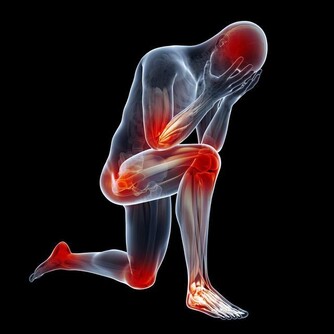

“空調腿”是指室內開啟空調後,地面水平溫度最低,人的雙腿長期低暴露在外,

容易受涼刺激,出現雙腿酸痛,嚴重時膝關節疼痛、腫脹,使人難以忍受。

絕大多數“空調腿”是膝關節受寒冷刺激導致的滑膜炎、滑囊炎以及腿部肌肉受冷痙攣。

當人體遇冷時,血管收縮,血流速度減慢,血液中輸送的人體所需的各種養料和氧氣就會減少,而膝關節支撐人的身體,本身周圍血管少,血流速度就差,若穿著短褲、短裙則會使膝關節暴露在低溫環境,膝關節長時間受寒涼刺激,血液循環更慢,更易出現水腫和炎症改變,導致滑囊炎、滑膜炎等關節性疾病。